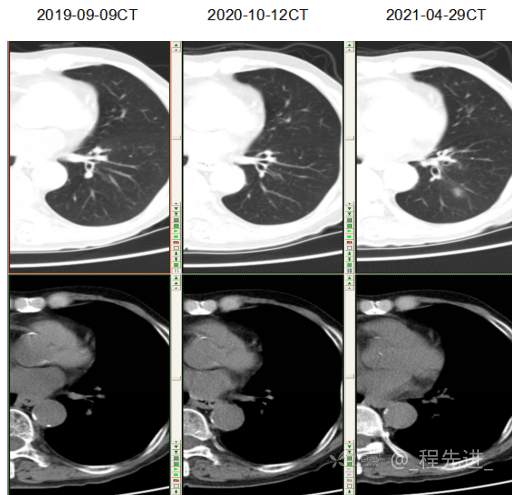

主诉: 反复咳嗽、咳痰10余年,加重10余天

现病史:患者10年前开始出现反复咳嗽、咳痰,3年前出现活动性气喘,休息后症状可缓解;冬春季节或受凉后症状加重,不伴反复下肢浮肿,曾在我院住院诊断为”慢性阻塞性肺疾病”,给予解痉平喘、化痰、输氧治疗有效,平素生活能自理,不能从事体力劳作,此次发病于10天前可能受凉后咳嗽、咳痰加重,咳黄痰,呈阵咳,咳白痰,活动气喘加重,不伴畏寒、发热,无胸痛,今来我院就诊,拟“慢性阻塞性肺病伴急性加重”收住入院,自发病以来,患者精神、食纳、睡眠一般,大小便如常,体重有下降,县体不详。患者及陪护人员:否认14天内离开过南丰,否认14天内有新型冠状病毒感染病例报告社区或中高风险地区的旅行史或居住史,否认14天内与新型冠状病毒感染的患者或无症状感染者有接触史,否认14天内曾接触过来自有病例报告社区或中高风险地区的发热或有呼吸道症状的患者,否认14天内在小范围如家庭、办公室、学校班级等场所,出现5例及以上发热和/或呼吸道症状的聚集性发病病例。